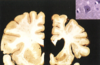

C = nucleo caudado P = Putamen S = nucleo estriado ## Footnote En la foto de abajo hay perdida del nucleo caudado. Comparar con la foto de arriba Ventriculos dilatados por perdida de masa encefalica = hidrocefalia ex vacuo

El encéfalo es pequeño y muestra una atrofia llamativa del núcleo **caudado** y del **putamen**, componentes del cuerpo estriado posterior; el globo pálido puede atrofiarse secundariamente, y los ventrículos laterales y el tercer ventrículo están **dilatados**

Figura 28.41 - Enf. de Huntington, hemisfério normal (izquierda) comparado con un hemisferio con **enfermedad de Huntington (derecha)** en el que se observa **atrofia del cuerpo estriado y dilatación ventricular**. Recuadro. Inclusiones intranucleares en las neuronas destacadas mediante tinción inmunohistoquímica para ubicuitina